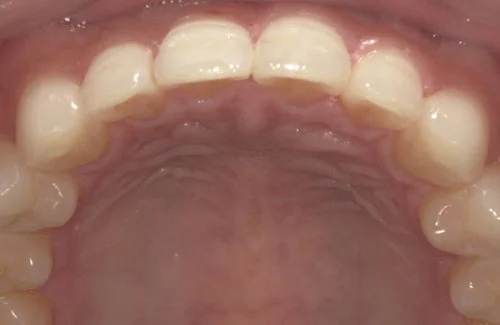

治療前後の写真

<症例3>前歯のクロスバイトでお悩み

右上の前歯2本が反対に咬合している、いわゆるクロスバイトが主訴でご来院なさいました。

主訴以外の部分には大きな叢生はなく、また患者様も装着時間をしっかり守ってくださったので約6ヶ月で改善することができました。

患者様と症状

主訴:上の前歯が出ている

性別・年齢:20代女性

問題点:上顎左側側切歯のクロスバイト、叢生

診断:前歯部の叢生を伴うアングルⅠ級の不正咬合

主なリスク:矯正中一時的に咬合しにくくなる、歯肉退縮

症状:叢生(そうせい) 上顎前突(じょうがくぜんとつ)

治療内容

治療期間:6ヶ月

治療費用:495,000円(税込)

プラン:14枚コース/ライトプラン

抜歯:親知らずのみ抜歯

再診治療費:無し

追加治療費:無し

保定装置費:無し

・2本の前歯が前突しておりましたが、矯正で自然な歯並びになりました。

・前歯の1本が下の歯の裏側に噛み合うクロスバイトになっていましたが、矯正で改善されました。